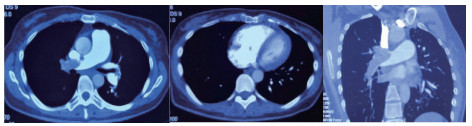

1 经典的挽救性溶栓治疗策略可能带给医生更多的是被动和难度例1 男性,28岁,体质量90 kg。主诉“胸闷、憋气1周加重1 d”。既往:体健;喜久坐(平均10~15 h/d);否认手术史、外伤史;入院查体:神志清楚,体温36.8℃,血压128/80 mmHg(1 mmHg=0.133 kPa),脉搏120次/min,呼吸26次/min,脉氧饱和度96%(安静,空气氧),未见明显乏氧征。双肺呼吸音清,未闻及干湿性啰音。心率120次/min,心律齐,P2 > A2,心界无扩大,无杂音。腹软,无压痛,肠鸣音正常,双下肢无浮肿。神经系统查体未见异常。血气分析(空气氧)提示pH 7.514,PaCO2 27.2 mmHg,PaO2 67.1 mmHg,SaO2 95.0%;D-Dimer:3 035 ng/mL,FDP 33.08 μg/mL,FBG 4.520 g/L;PLT 179.0 G/L,TNI 0.08 ng/mL,BNP 882.00 pg/mL;ALT 38 U/L,AST 17 U/L,CREA 82.6 μmol/L,血Na+、K+、Cl-正常范围;超声心动图(Ultrasonic Cardiogram,UCG)提示:右心增大,肺动脉主干及右肺动脉增宽,肺动脉主干32 mm,三尖瓣反流(重度),反流面积8.6 cm2,TI法估计SPAP为67 mmHg、左室舒末内径50 mm、左室E/A:45/38 cm/s, 左室壁厚度及运动正常,未见节段性室壁运动障碍;双下肢静脉超声提示左侧股静脉血栓形成可能(完全型)。心电图(图 1所示)提示窦性心动过速;肺动脉增强CT(Computed tomographic pulmonary angiography, CTPA)提示双肺主干明确充盈缺损(图 2所示)。入院诊断:急性肺血栓栓塞症(中高危)。入院后给予抗凝治疗(依诺肝素钠90 mg,皮下注射,1次/12 h)重叠华法令治疗的第4天D-Dimer升至47 482 ng/mL,第6天2 411 ng/mL。第7天常规复查双下肢超声未见新增血栓形成,复查UCG(当天INR 2.25)提示右心房漂浮血栓,并随心脏蠕动明显(图 3所示)。在准备胸外科手术取栓的过程中出现血压下降至70/40 mmHg,脉氧饱和度降至45%,立即给予气管插管并系统溶栓治疗(r-tPA 100 mg于2 h输注),溶栓治疗1.5 h患者血压逐渐回升并趋于稳定、溶栓治疗3 h自主呼吸开始恢复,于插管3天后(住院第10天)拔出气管插管,成功撤离呼吸机。溶栓过程中曾经出现消化道、气道出血,血红蛋白下降1.9 g/dL,未予输血治疗。溶栓后复查CTPA提示双肺主干血栓负荷明显减少,远段血液灌注明显增加(图 4所示)。

| 图 2 入院时CTPA提示双肺主干明确充盈缺损 |

| 图 4 溶栓后的CTPA肺动脉主干血栓负荷明显减少、远段血液灌注明显增加 |